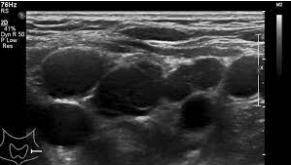

Primary malignant lymph node (lymphoma)

Malignant features:

• *Multiple very hypoechoic nodes**

• *-** Absent hilum/ central necrosis

• Heterogeneous

• *Round**

• >1cm AP diameter

• Taller than wide

Lobulated/ irregular contour

Disorganised vascularity

Differential = mets (calcs)